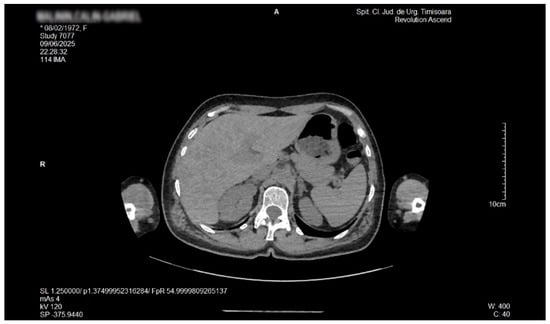

Liver Lipodystrophy in Barraquer–Simons Syndrome: How Much Should We Worry About?

Lipodystrophy is a rare group of metabolic disorders characterized by the abnormal distribution of body fat, which can lead to various metabolic complications due to the body’s inability to adequately process carbohydrates and fat. We report the case of a female, aged 53 years, who was admitted as an outpatient for progressive weight loss of the upper part of the body (face, neck, arms, and chest), dyspeptic complaints, fatigue, mild insomnia, and anxious behavior. Her medical history was characterized by the presence of dyslipidemia, hypertension, and a minor stroke episode. However, she denied any family-relevant medical history. Although the clinical perspective suggested a possible late onset of partial acquired lipodystrophy, due to the imaging exam that revealed an enlarged liver with inhomogeneous structure with multiple nodular lesions, scattered over both lobes, a lot of lab work-ups and complementary studies were performed. Eventually, a liver biopsy was performed by a laparoscopic approach during cholecystectomy, the histology consistent with metabolic disease-associated steatohepatitis (MASH). In conclusion, given their heterogeneity and rarity, lipodystrophies may be either overlooked or misdiagnosed for other entities. Barraquer–Simons syndrome (BSS) may be associated with liver disease, including cirrhosis and liver failure. Liver lipodystrophy in BSS may sometimes feature steatosis with a focal, multi-nodular aspect, multiplying the diagnostic burden. Liver lipodystrophy may manifest as asymptomatic fat accumulation but may progress to severe conditions, representing one of the major causes of mortality in BSS, apart from the cardio-vascular comorbidities. Given the potential of severe outcomes, it is mandatory to correctly assess the stage of liver disease since the first diagnosis. Full article